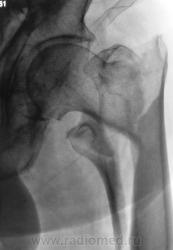

1. Эх, гололёд, гололёд, гололёд...

Опять все обледенело. Травмы, травты, травмы...

Ваше мнение коллеги?